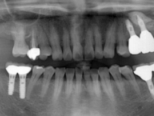

症例写真(レントゲン)